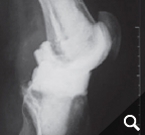

In order to diagnose these infections, tissue samples are taken from the joint in addition to a puncture, as only close cooperation between orthopedists, pathologists and microbiologists can ensure the correct diagnosis. In addition, we also devote ourselves to obviously infected prostheses, of course. These infections can occur shortly after the operation (so-called early infection up to 6 weeks postoperatively) but also years after the operation (as so-called late infection). In addition to the smallest entry points (e.g. an ulcerated toenail), serious infections such as pneumonia can also lead to bacteria colonizing the surface of the prosthesis. Patients with a limited immune system (e.g. diabetics, rheumatics) are particularly at risk. If an infection is noticed early enough after surgery, it is occasionally still possible to eliminate the infection without removing the prosthesis by carefully cleaning the wound and changing the moving parts.

However, infections often go unnoticed for many weeks, so that removal of the prosthesis is unavoidable. Depending on the pathogen and its sensitivity, a placeholder containing antibiotics is then implanted, which remains in place for 6 weeks. Antibiotics in tablet form must then also be taken for this period. However, it is not necessary for a patient to remain in the hospital during this entire period. If home care is not possible, for example, it is also possible to organize this in close cooperation with our social services. After 6 weeks it is generally possible to reimplant a prosthesis, provided that the blood values show that the infection is under control. Antibiotics must then be taken again for 6 weeks after surgery. Which antibiotics are taken is determined in close cooperation with colleagues in microbiology and clinical pharmacology, with whom regular rounds and therapy checks are carried out. These therapeutic measures are carried out in a special area of the clinic using the most modern methods.